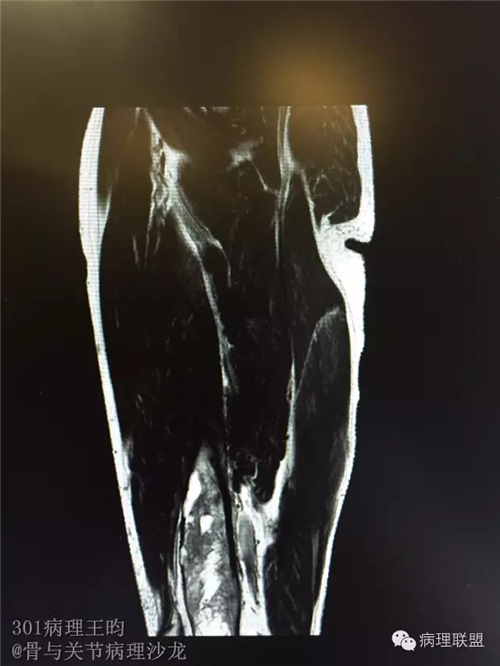

右股骨髓内高分化低级别骨肉瘤or骨纤维异常增殖症(Fibrous Dysplasia)?

男,36岁,活动后疼痛,发现右股骨远端肿瘤。